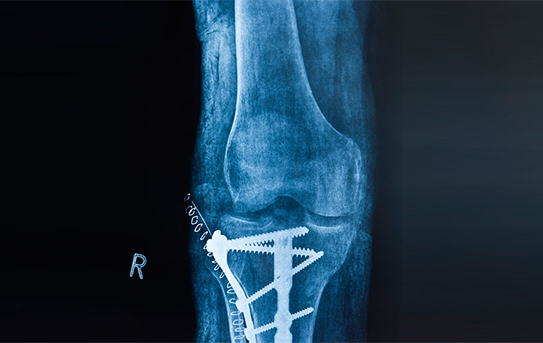

- Fractures Around Hip And Knee Replacements

- Surgical And Nonsurgical Fracture Care